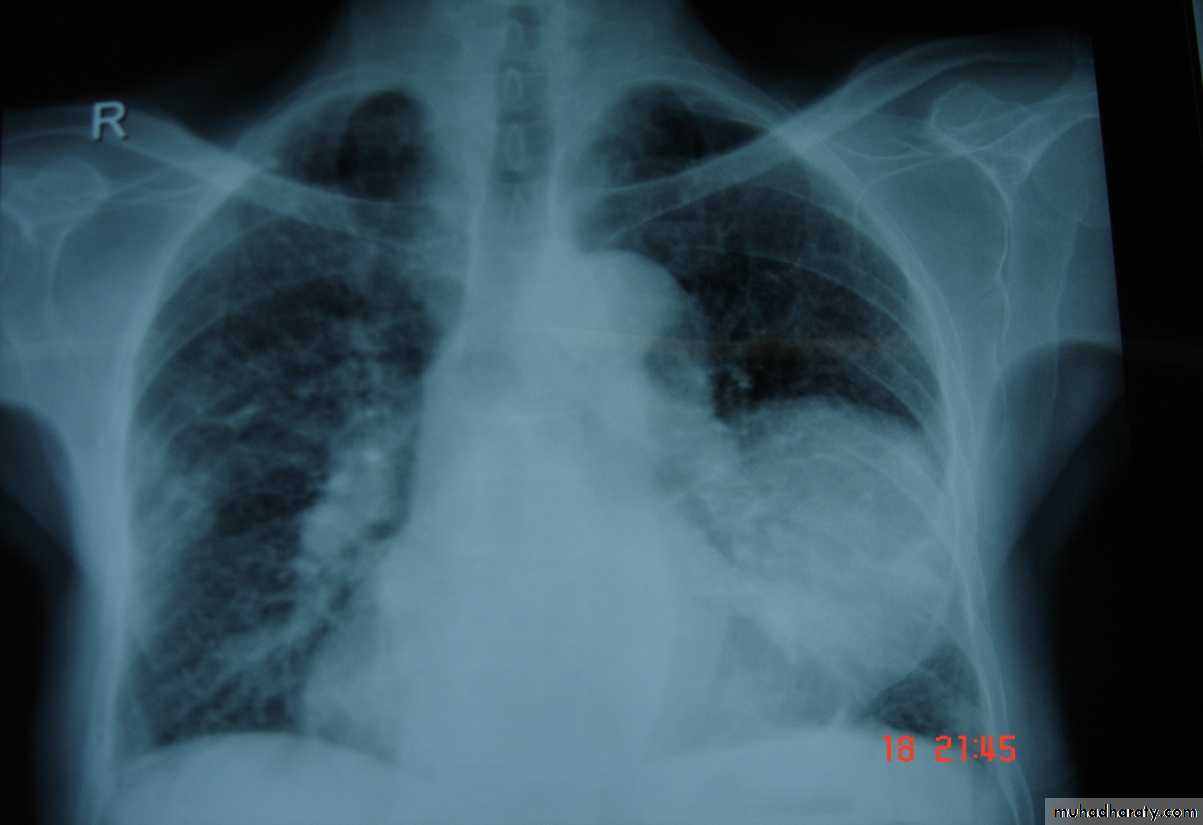

• A-Asymptomatic• Any smooth homogenous opacity of uniform density with clear cut border and little or no reaction around it on a chest X-Ray is a hydatid cyst unless proved the other wise .

• Radiological Findings

• 1-Smooth homogenous opacity (Intact H.C).• 2-Partial rupture (per vesicular pneumocyst).

• 3-Complete rupture (Water –lilly sign) .

• 4-Formation of lung abscess(Air –fluid level) .

• 5-Completely coughed out cyst(empty cavity )

• 6-Rupture into the pleura (hydropneumothorax)